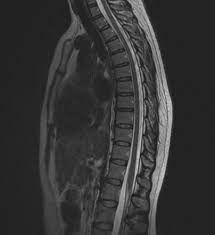

Costovertebral Joint Dysfunction

The thoracic spine consists of 12 vertebrae and are the main attachment points for the ribs, hence it is naturally more stiff than the lumbar and cervical spine with limited movement. The costovertebral joint is an articulation between the vertebrae and the rib, connected by a synovial joint which allows some small degree of movement, mainly medial and lateral rotation, which is mainly utilised during respiration. Due to the complexities of the thoracic neural network, costovertebral joint dysfunction can sometimes be overlooked as a source of posterior chest wall pain.